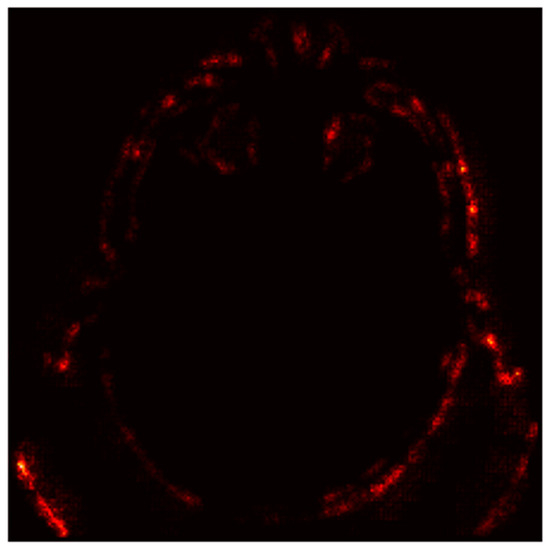

4.4. Stroke Prediction Visualization

4.6.3. Gradient-Based Saliency Maps

- Red Areas: These regions, such as the hyperdense clot in the left hemisphere, are critical for the “Stroke” prediction. The model assigns high importance to these areas, aligning with clinical expectations that hyperdense regions indicate hemorrhagic strokes.

- Green/Blue Areas: These regions have minimal impact on the prediction, indicating that the model focuses on specific anatomical features rather than the entire image.

- Bright Spots (High Gradients): These regions correspond to areas where small changes in pixel values significantly alter the model’s output. For instance, the hyperdense clot (bright spots) is highlighted as a critical region for the “Stroke” prediction.

- Dark Regions (Low Gradients): These areas, such as the background or non-stroke-related anatomy, have little to no impact on the prediction, confirming the model’s focus on stroke-prone regions.